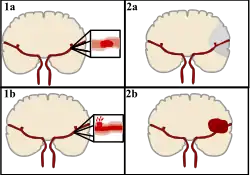

Stroke can be classified into two major categories: ischemic and hemorrhagic.[20] Ischemic stroke is caused by interruption of the blood supply to the brain, while hemorrhagic stroke results from the rupture of a blood vessel or an abnormal vascular structure.

About 87% of stroke is ischemic, with the rest being hemorrhagic. Bleeding can develop inside areas of ischemia, a condition known as "hemorrhagic transformation." It is unknown how many cases of hemorrhagic stroke actually start as ischemic stroke.[2]

Hemorrhagic

There are two main types of hemorrhagic stroke:[30][31]

- Intracerebral hemorrhage, which is bleeding within the brain itself (when an artery in the brain bursts, flooding the surrounding tissue with blood), due to either intraparenchymal hemorrhage (bleeding within the brain tissue) or intraventricular hemorrhage (bleeding within the brain's ventricular system).

- Subarachnoid hemorrhage, which is bleeding that occurs outside of the brain tissue but still within the skull, and precisely between the arachnoid mater and pia mater (the delicate innermost layer of the three layers of the meninges that surround the brain).